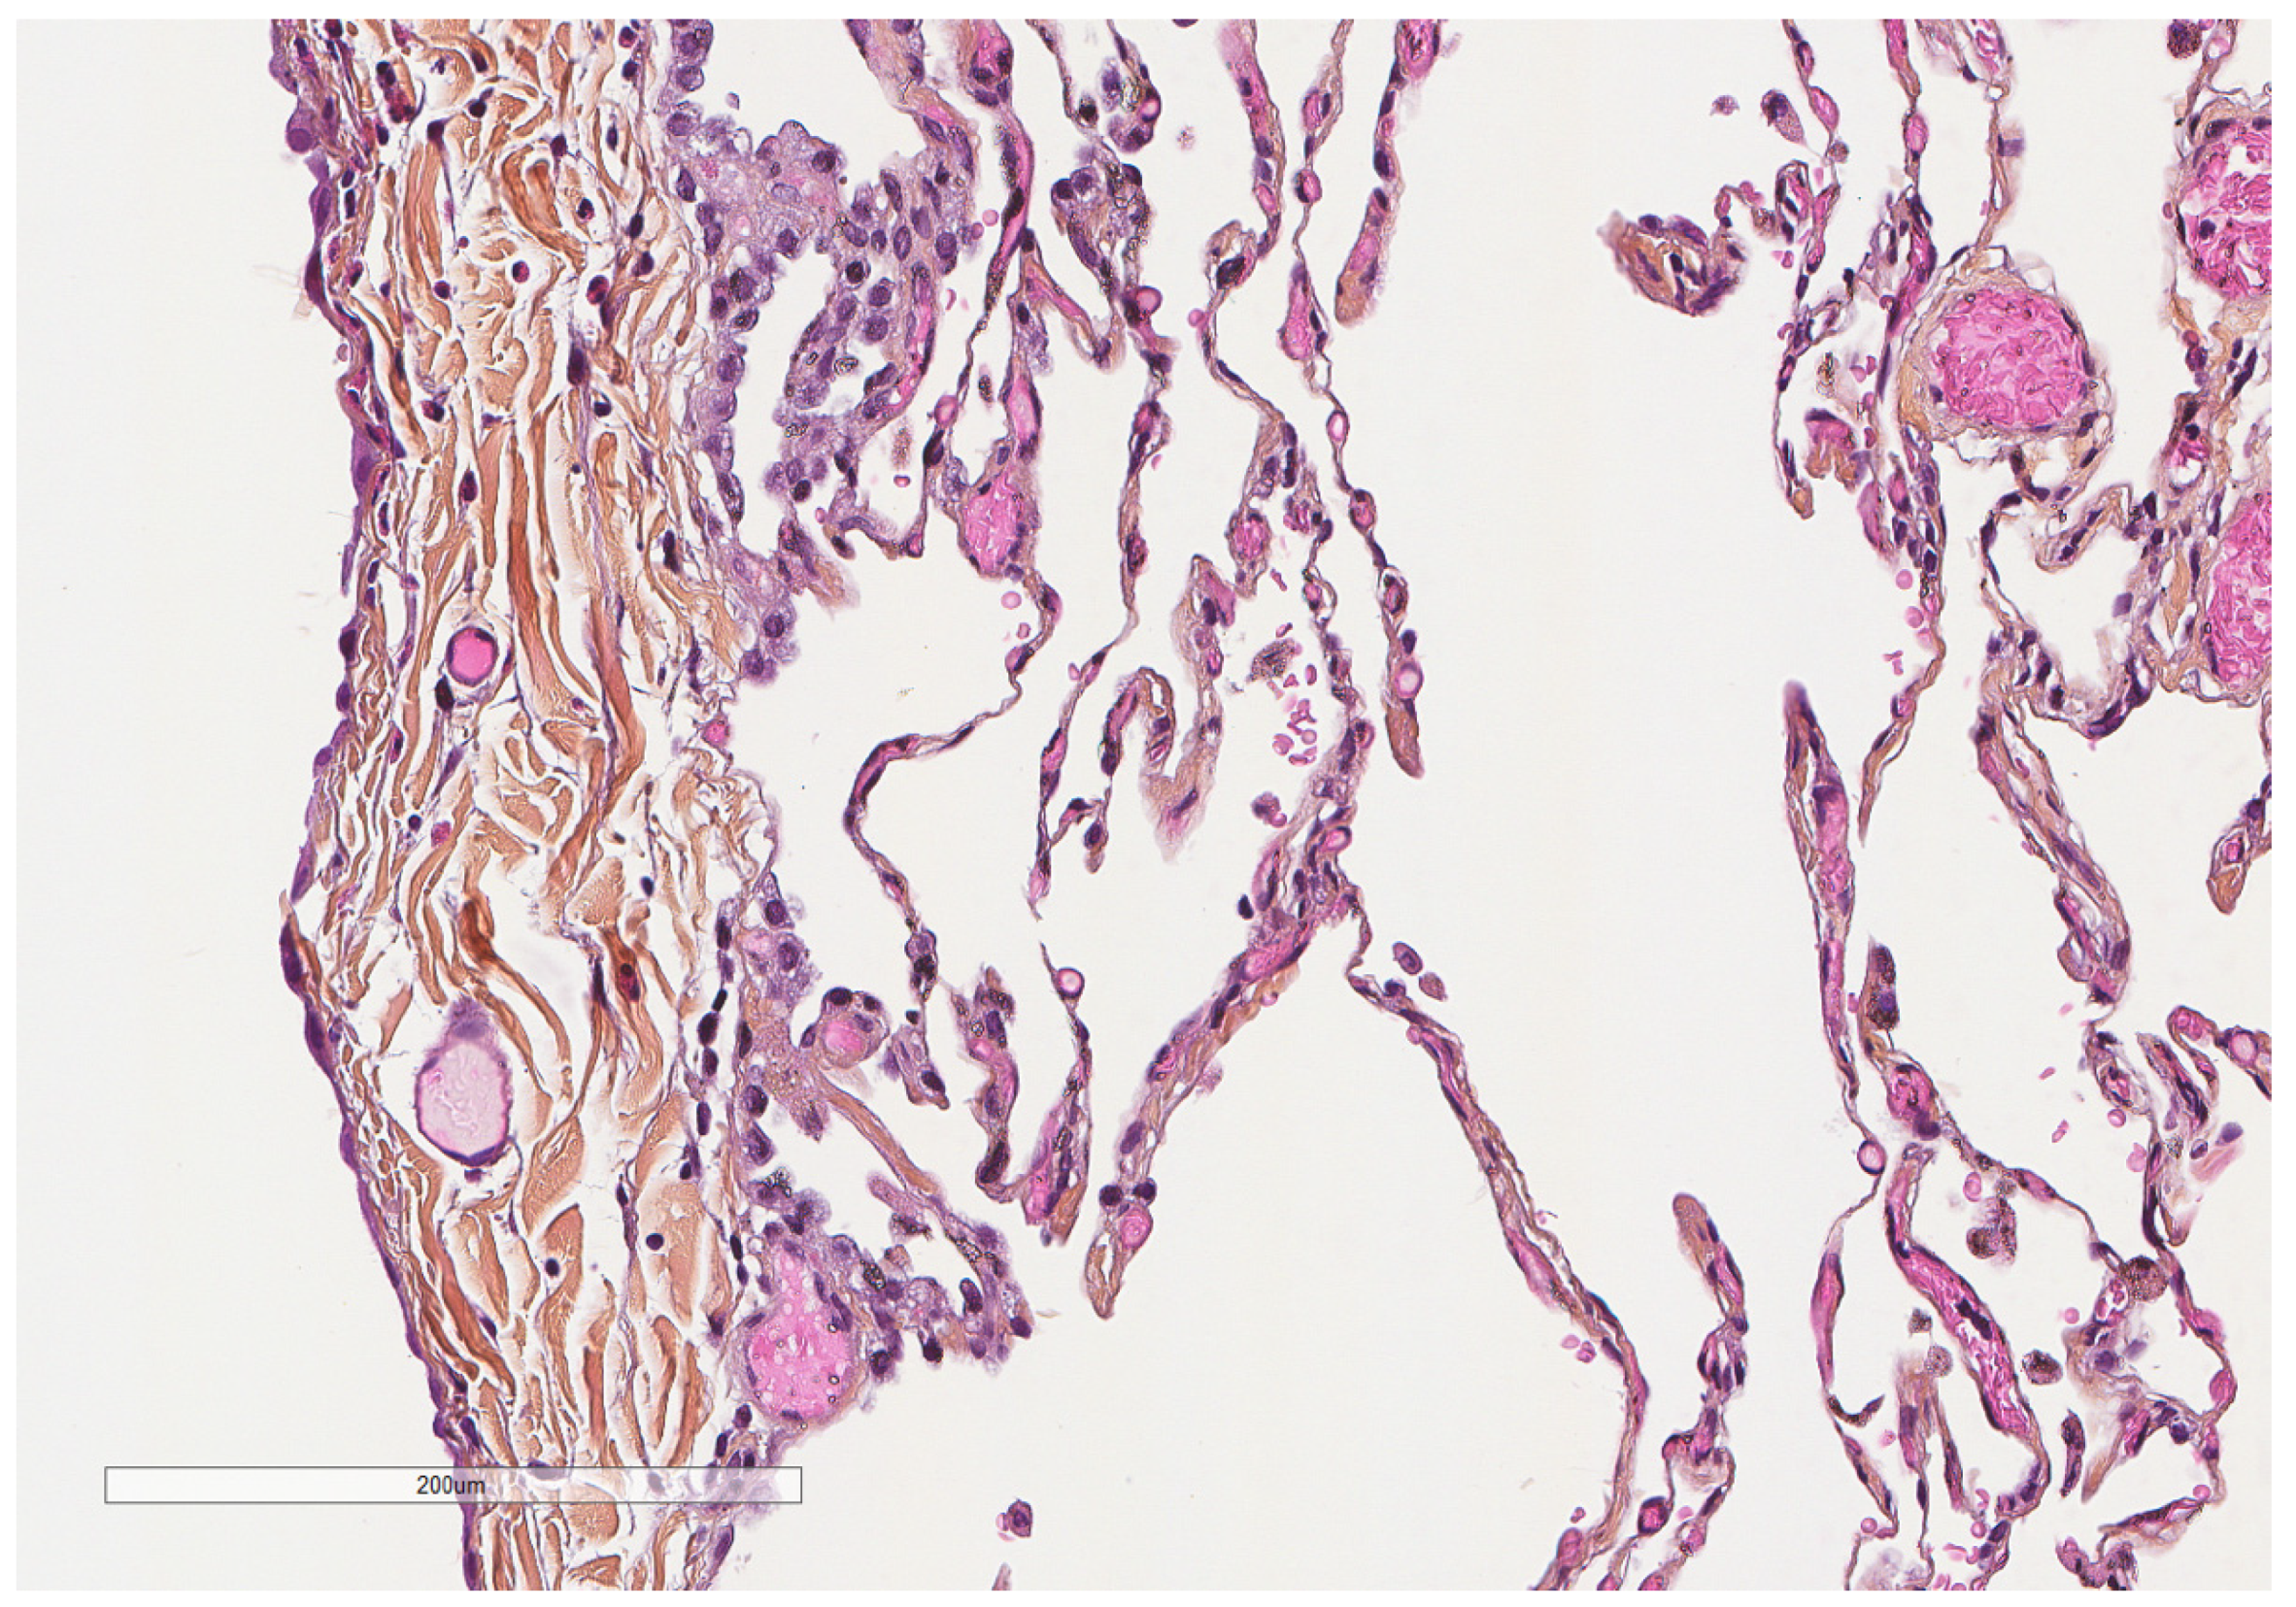

- Karpathiou, G.; Hathroubi, S.; Patoir, A.; Tiffet, O.; Casteillo, F.; Brun, C.; Forest, F.; Rahman, N.M.; Peoc’h, M.; Froudarakis, M.E. Non-specific pleuritis: Pathological patterns in benign pleuritis. Pathology 2019, 51, 405–411. [Google Scholar] [CrossRef] [PubMed]